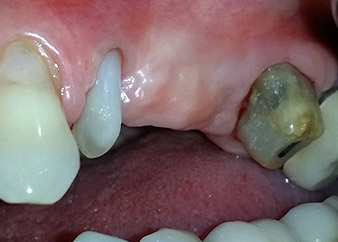

A 58-year-old female patient complained of pain and increased mobility of her bridge abutment tooth 24. Periodontal inflammation was present with pocket depths of 7 mm mesiobuccally and more than 12 mm distally, as well as third-degree furcation involvement. Moreover, the radiograph revealed an extensive periodontal lesion around the apical region of the (alio loco) endodontically pretreated tooth 24 (Fig. 1).

One year earlier, teeth 25 and 26 had been extracted due to trauma and for endo-perio reasons, prior to the placement of the bridge. A combined endo-perio lesion was diagnosed for tooth 24, of unclear aetiology. The patient wanted to keep her bridge abutment teeth 24 and 27 and would not accept a final, or even temporary, removable prosthesis. Therefore, it was agreed to make all efforts to retain both teeth, in spite of their poor prognosis as based on radiological and clinical findings.

Placement of two submerged implants was planned at sites 25 and 26, in a surgical session with open periodontal debridement and apicoectomy of tooth 24. Due to the vertical bone deficiency at the future implant site, an internal sinus augmentation was also planned.

One month later, on the day of surgery, pain and inflammation at tooth 24 were minimal, but mobility of Miller class 2 was still present. After opening the flaps and cleaning the periapical and peri radicular infected tissue, the extent of the bone defect became obvious (Figs. 2 and 3).

At the buccal root, all vestibular and distal bone was missing. Attachment was essentially restricted to the palatal root, underlining the preliminary poor prognosis. Tooth 27 also showed a reduced horizontal attachment and a minimal apical rarefaction (cf. Fig. 1) without clinical symptoms.